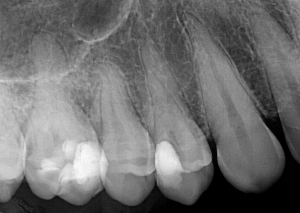

Интраорална сегментна рентгенография по Dick

Основните клинични показания на зъбните снимки са рентгенографска визуализация на целият зъб – включващ коронкова и коренова част на зъба. Този вид зъбни снимки се използват за откриване на патологични изменения в зъбите, периапикални абсцеси и кисти, при ендодонтско лечение, за отценка на пародонта на дадения зъб, при необходимост от зъбна екстракция или друга хирургична интервенция, травма на зъбите, както и проследяване на оздравителния процес след проведено лечение на зъба и пародонта